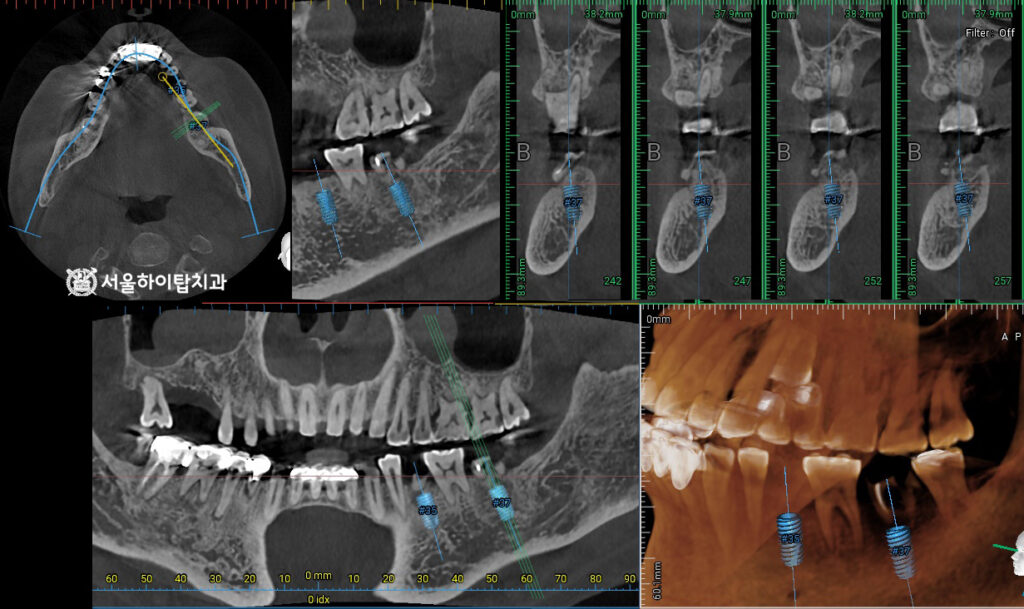

계획 수립 및 CBCT 촬영

먼저, 아래턱의 경우 뿌리만 남아 있는 치아들을 모두 빼내어

임플란트를 식립할 수 있는 환경을 조성하는 것이 첫 번째 단계입니다.

그다음으로 CT 촬영을 통해 식립에 알맞은 위치, 각도, 깊이를 확인하고,

동시에 하지조신경관 등 주변 해부학 구조물을 안전하게 확인하게 됩니다.

이 과정에서 필요시 골 이식 등 추가 처치 과정을 고려할 수 있습니다.

위턱도 동일한 방식으로 진행되지만,

기울어진 사랑니 때문에 공간이 다소 부족한 상태입니다.

부평 치과 에서는 두 개의 어금니 자리에 각각 식립하는 것이 이상적이라 말씀드리지만,

공간 제약으로 인해 1개만 식립하고, 추후 크라운을 크게 만들어주면

빈 공간을 최소화하고 저작과 심미를 동시에 회복할 수 있습니다.

수술 완료

정밀한 CT를 통해 나온 데이터에 따라 정확한 위치에 심긴 모습입니다.